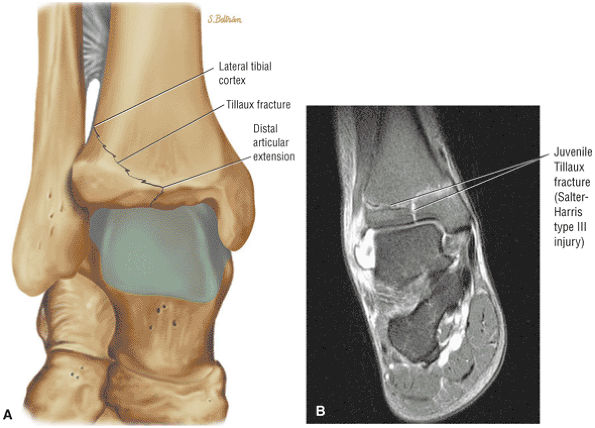

![]() |

|

FIGURE 5.28 Tibiotalar Joint.

FIGURE 5.29 Impingement.